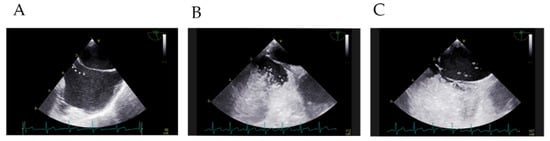

2.2. Imaging and Measurements